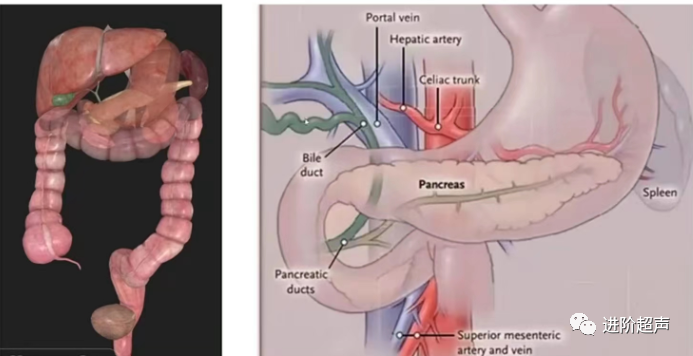

胰腺超声上机操作

正常胰腺切面扫查

胰腺的长轴切面,胰头、颈、体、尾部的短轴切面,以及左肋间通过脾窗的胰尾切面